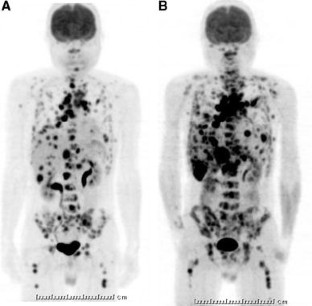

Fig. 1

Fig. 2

Fig. 3

Fig. 4